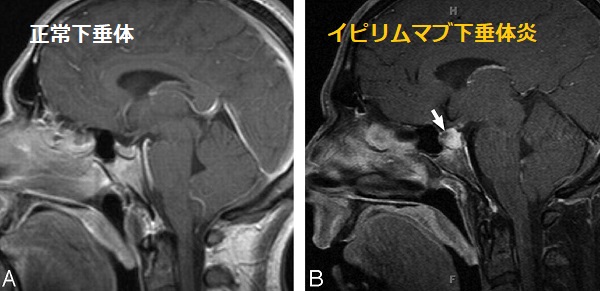

自己免疫性下垂体炎(下垂体irAE)

自己免疫性下垂体炎は、イピリムマブ(ヤーボイ®)の3.8%に起こります(JAMA Oncol. 2018 Feb 1;4(2):173-182.)。

一方、ニボルマブ(オプジーボ®)、ペムブロリズマブ(キイトルーダ®)の1%前後。

MRI所見は特徴的で、造影T1強調像では腫大した下垂体が不整に増強されます。

(写真AJNR Am J Neuroradiol. 2009 Oct;30(9)1751-3.)